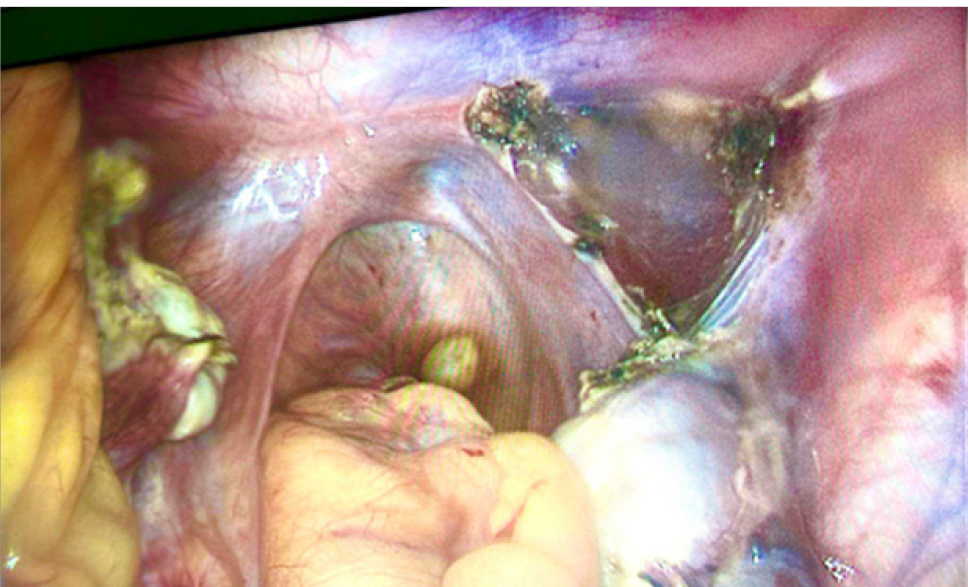

В связи с наличием объемного образования малого таза больших размеров, 11.10.2022 г. после полного лабораторного и клинического обследования, в плановом порядке выполнена лапароскопия. Интраоперационно обнаружено: матка представлена рудиментом – соединительно-тканным тяжом, из которого вправо исходит округлое образование около 8 см в диаметре – миоматозный узел (рис. 1). Правая маточная труба отходит от латерального полюса миоматозного узла, не изменена, с выраженными фимбриями. Влево от соединительно-тканного тяжа исходит рудиментарный мышечный рог матки с маточной трубой (без особенностей). Яичники с обеих сторон обычного строения, нормальных размеров. В связи с обнаруженным была выполнена миомэктомия, билатеральная тубэктомия. Миоматозный узел с маточными трубами извлечены из брюшной полости в стерильном контейнере (рис. 2).

Рис. 1. Интраоперационная визуализация округлого образования (миоматозный узел)